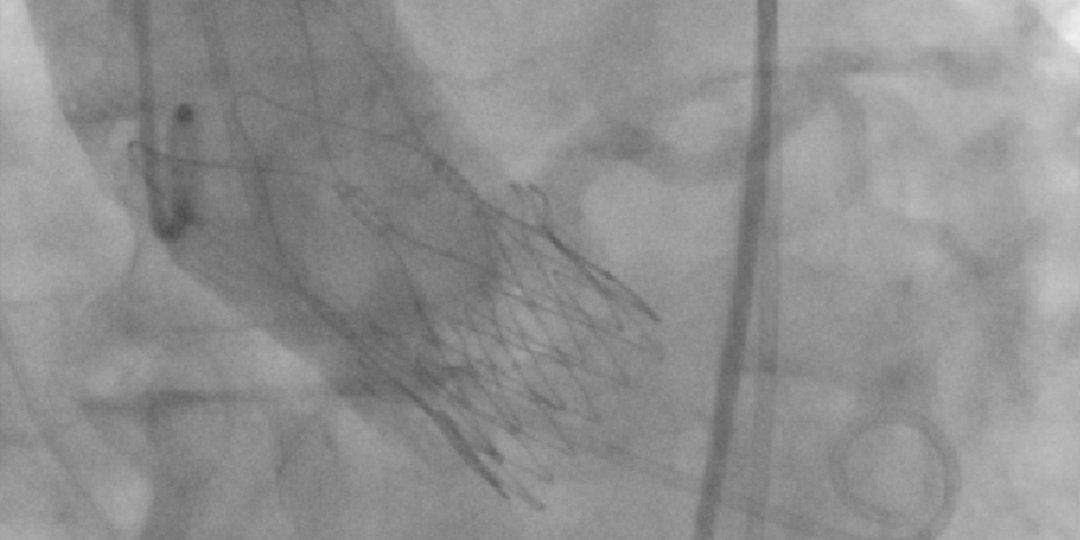

Sometimes #tavr is not just a straight shot. The advantage of the flexible delivery system of Boston #acurate. Bend in iliac, aorta, aortic arch, horizontal aorta. Bicuspid AS Vmax 5,6 m/s. Got the valve in, good result, no complication.